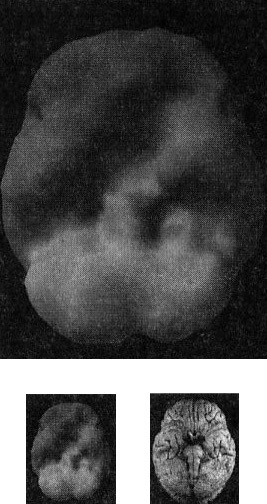

Второй тип томограмм — это трехмерные функциональные снимки, в которых компьютер сначала вычисляет среднюю активность мозга, а затем показывает верхние 15 % активности. Они помогают увидеть гиперактивные области, что полезно в диагностике припадков, разных типов тревожности и депрессии.

Здоровый трехмерный функциональный снимок (рис. 2.3 и 2.4) должен показывать активность (белым цветом) в задней части мозга (мозжечке) и визуальной, или затылочной, коре и среднюю активность в остальных местах (показано сеткой).

Трехмерное изображение функциональной активности здорового мозга ОЭКТ (вид поверхности сверху и снизу)

Рис. 2.3 Вид сверху

Рис. 2.4 Вид сверху